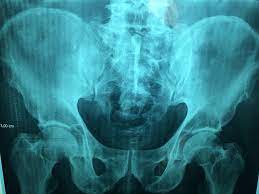

- X-레이 (X-ray): X-레이는 척추의 구조를 보는 데 사용됩니다. 디스크의 이상이나 척추 골절 등을 확인하는 데 도움을 줄 수 있지만, 디스크 자체의 세부 정보는 제공하지 않습니다.